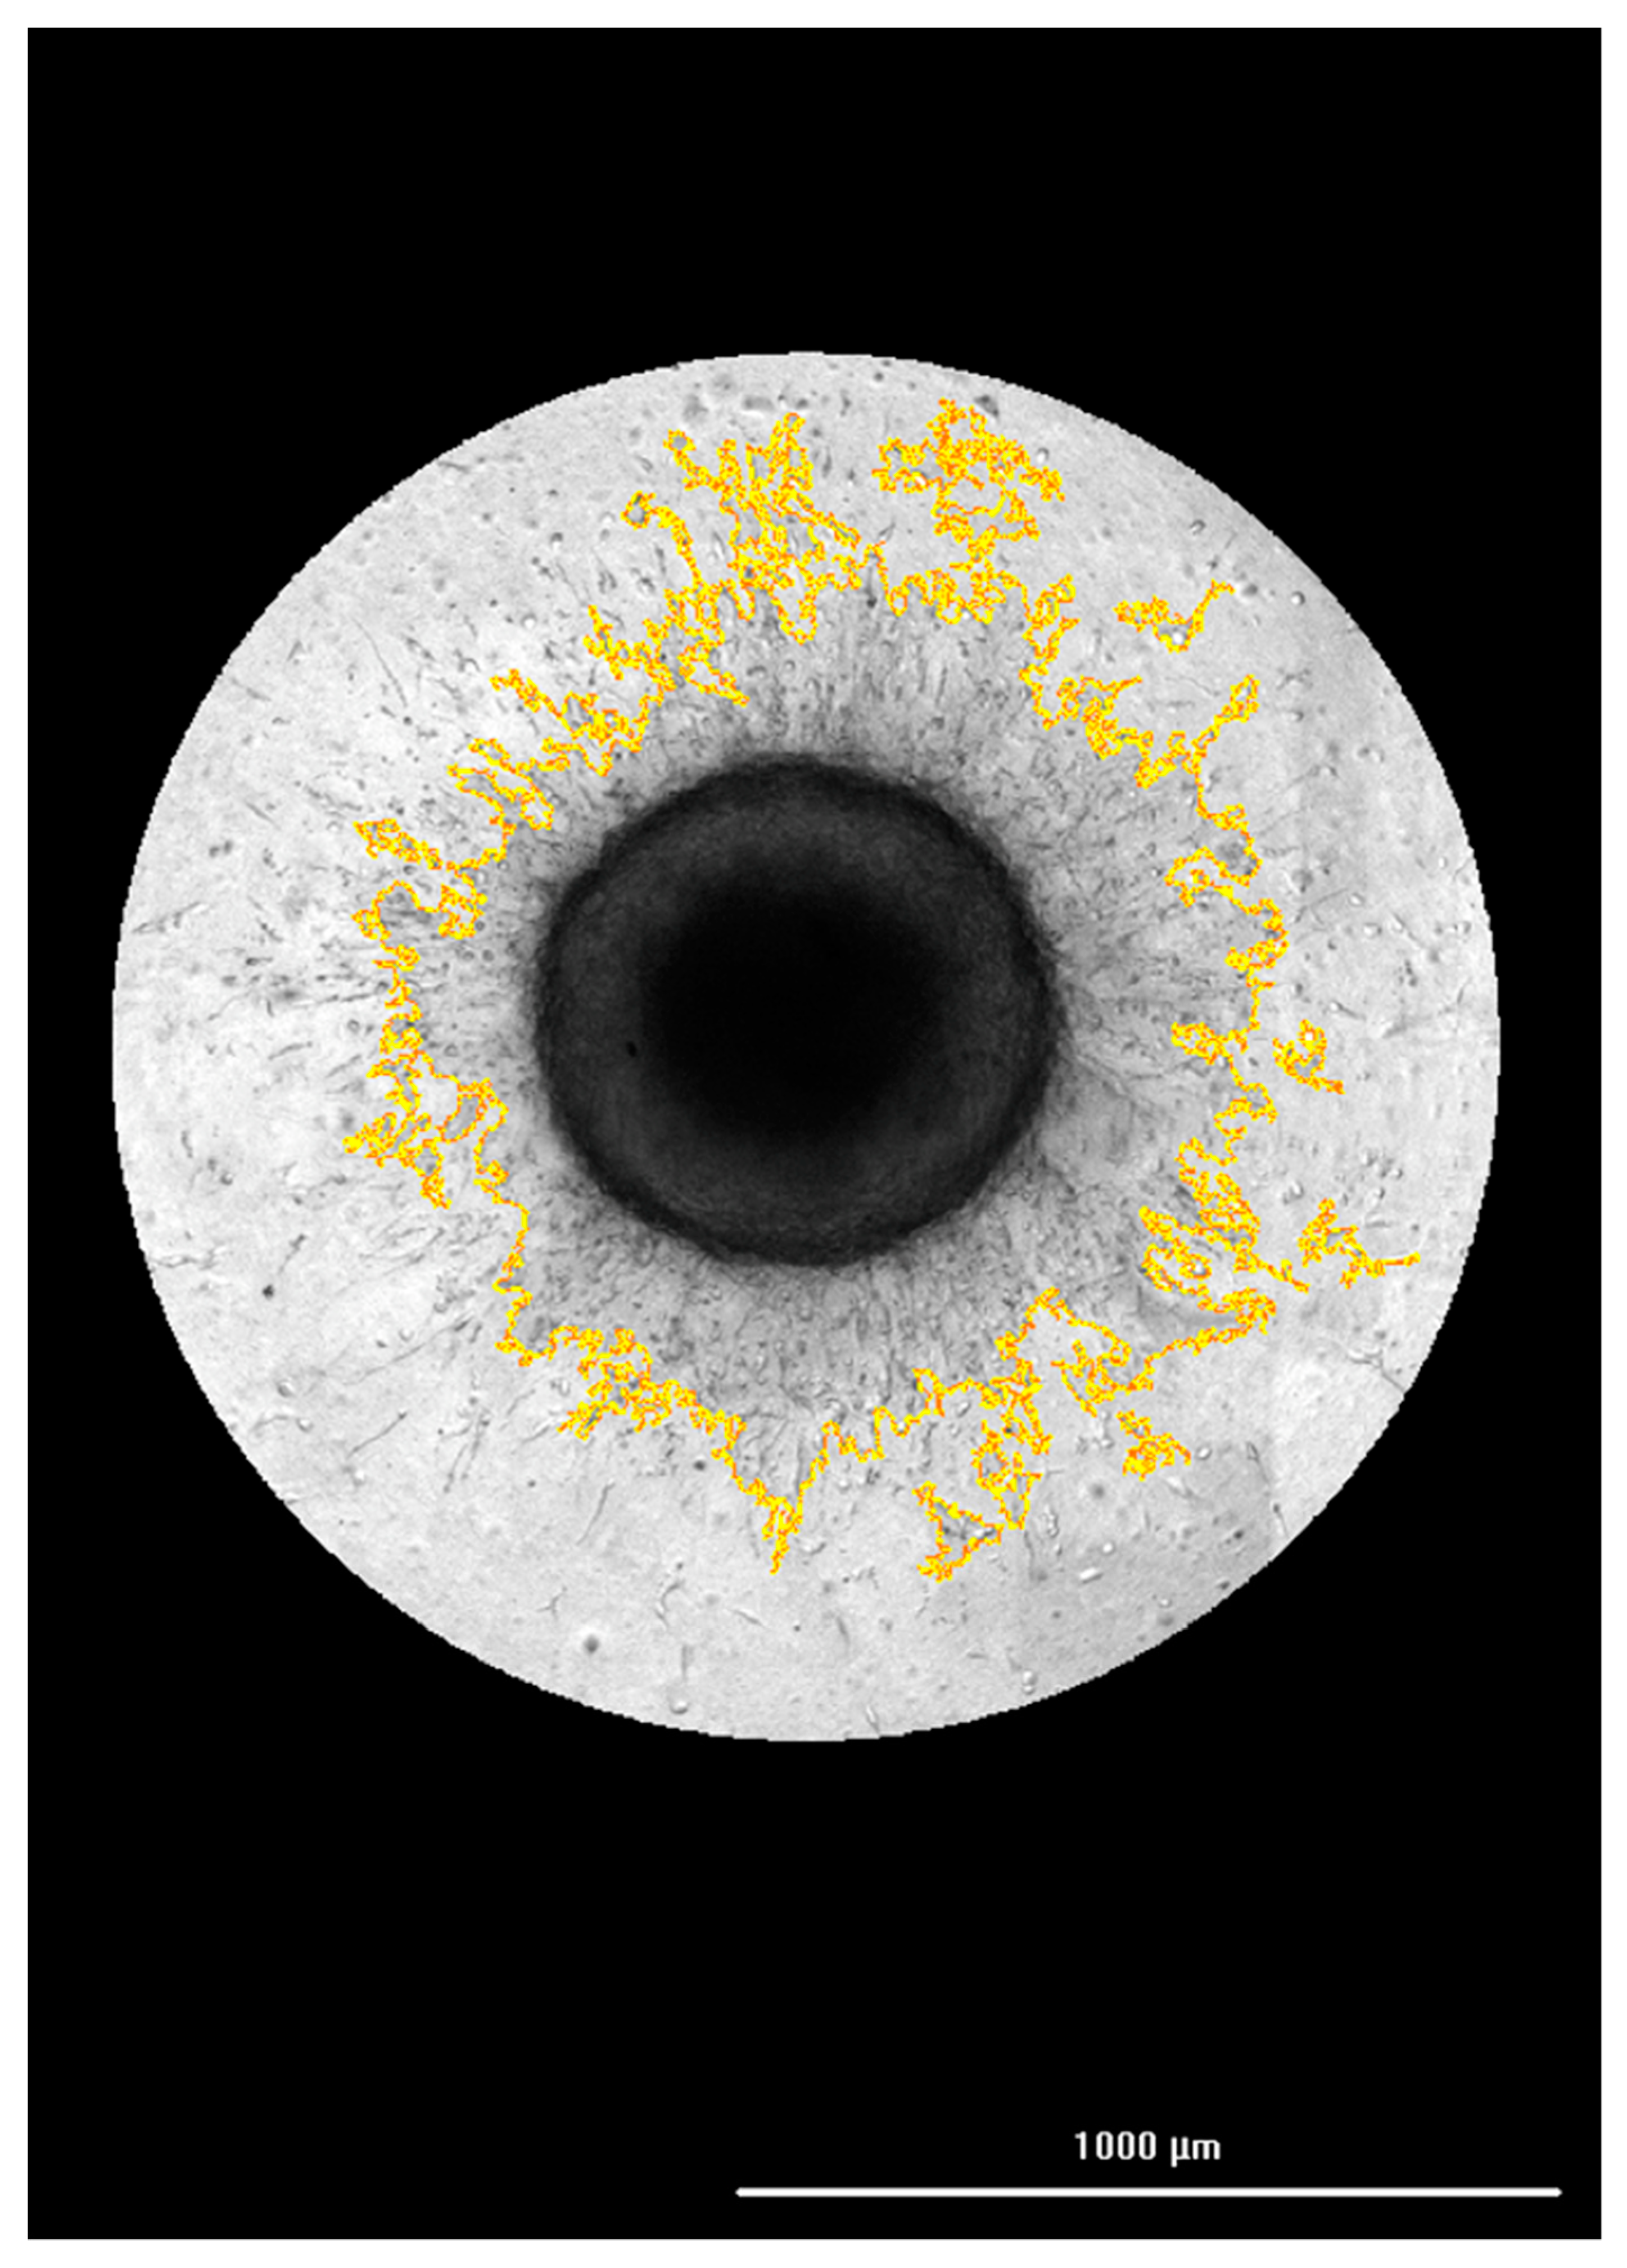

3.2. Correlation of FAM-fTHP-9 Signal with Increased Spheroid Invasion

3.4. Hit Pick Assay Performance Using FAM-fTHP-9 Signal to Trigger Imaging of Test Inhibitor Wells

3.6. Inhibition of FAM-fTHP-9 Signal and Spheroid Invasion in A172, H4, and SW 1088 Cell Lines